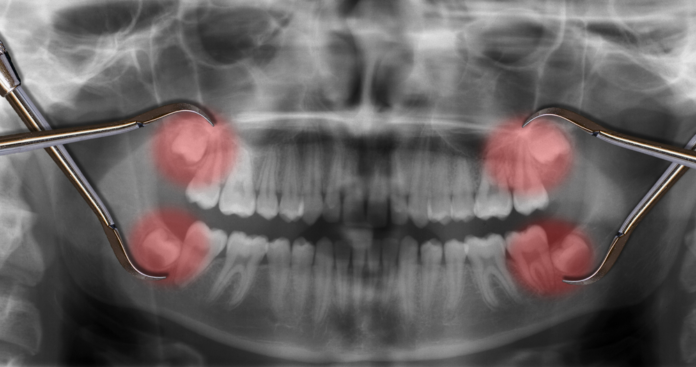

Umnjaci ili osmice: problemi,bolovi i lečenje

Veliki deo populacije nema dovoljno mesta u vilicama za ove zube i na kraju završi sa vađenjem istih. Ukratko možemo da kažemo “ukoliko imate...